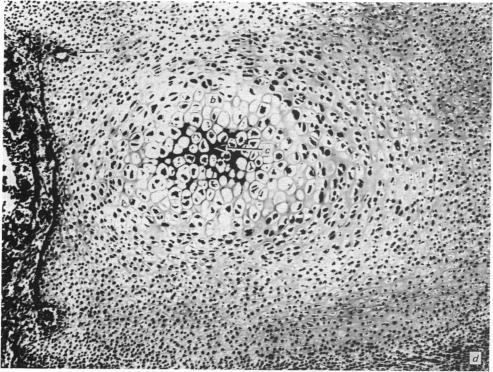

Bone formation in the vertebral centra commences within the centrum and is in this respect analogous to the secondary ossification which occurs in the epiphysis of a long bone. Bone tissue first appears at about the 85 mm C.R. stage and not in the 55 mm C.R. length embryo; at the latter stage blood vessels and calcification alone were observed. The connective tissue cells within the cartilage canal appear to assist osteogenesis by providing osteogenic cells which lay down bone in the walls of the cartilage canal, and provide cells which remove calcified cartilage found at the periphery of the canal; they assist growth by producing an appreciable number of chondrocytes that permit lateral expansion of the centra. Osteogenesis appears to occur in multiple foci within the growth plate of the older embryos and could account for the rapid rate of growth of vertebrae. Bone formation occurs in both mineralised and unmineralised matrix (as seen on the walls of the cartilage canals). The blood vessels within the growing vertebra tend to follow the zone of cartilage hypertrophy.